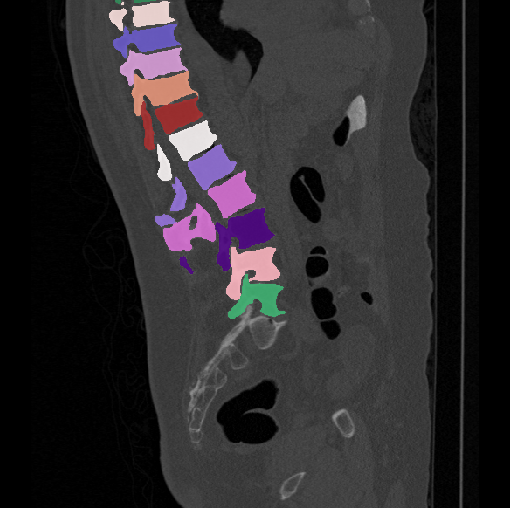

Images

GT

Predictions

We calculate the two metrics of each vertebra, and the results are reported in Table 2. On the one hand, our experimental results are close to those reported in reference (Sekuboyina et al., 2020) with the same model (nnUnet), verifying the high quality of our annotations. On the other hand, Table 2 shows it is difficult to segment the diseased vertebrae (the DSC of L6 is almost 0). Specifically, the existence of L6 confuses the model, resulting in prediction dislocations (see the last row in Fig. 4). Thus, our labeled dataset, which contains many L6 cases, is very valuable for the diseased vertebrae segmentation (we have stated those cases that are hard for annotation in the readme.txt file). Table 2 illustrates that the model trained with our annotations can achieve good performance on our CTSpine1K dataset but a much worse performance on the VerSe Challenge datasets, which explains there is an obvious domain gap between our annotated dataset and the public dataset. We infer the reason is that the COlONOG dataset is based on an empty stomach and colon, confusing the deep learning model by the changes of air content in the abdomen (see Fig. 3). Therefore, our annotations are a good complement to the existing datasets.

3.2.2 Qualitative results.

Some visualization results are presented in Fig. 4, where we can observe that the baseline model can achieve excellent segmentation results. Nevertheless, some failed predictions occur when spinal diseases exist, especially sacral lumbarization and lumbar sacralization. Besides, the image’s resolution of Z direction is closely related to the results, and a lower resolution leads to worse results. Maintaining a reasonable performance for a low resolution is a research challenge. Image superresolution (Peng et al., 2020) might be worth exploring.